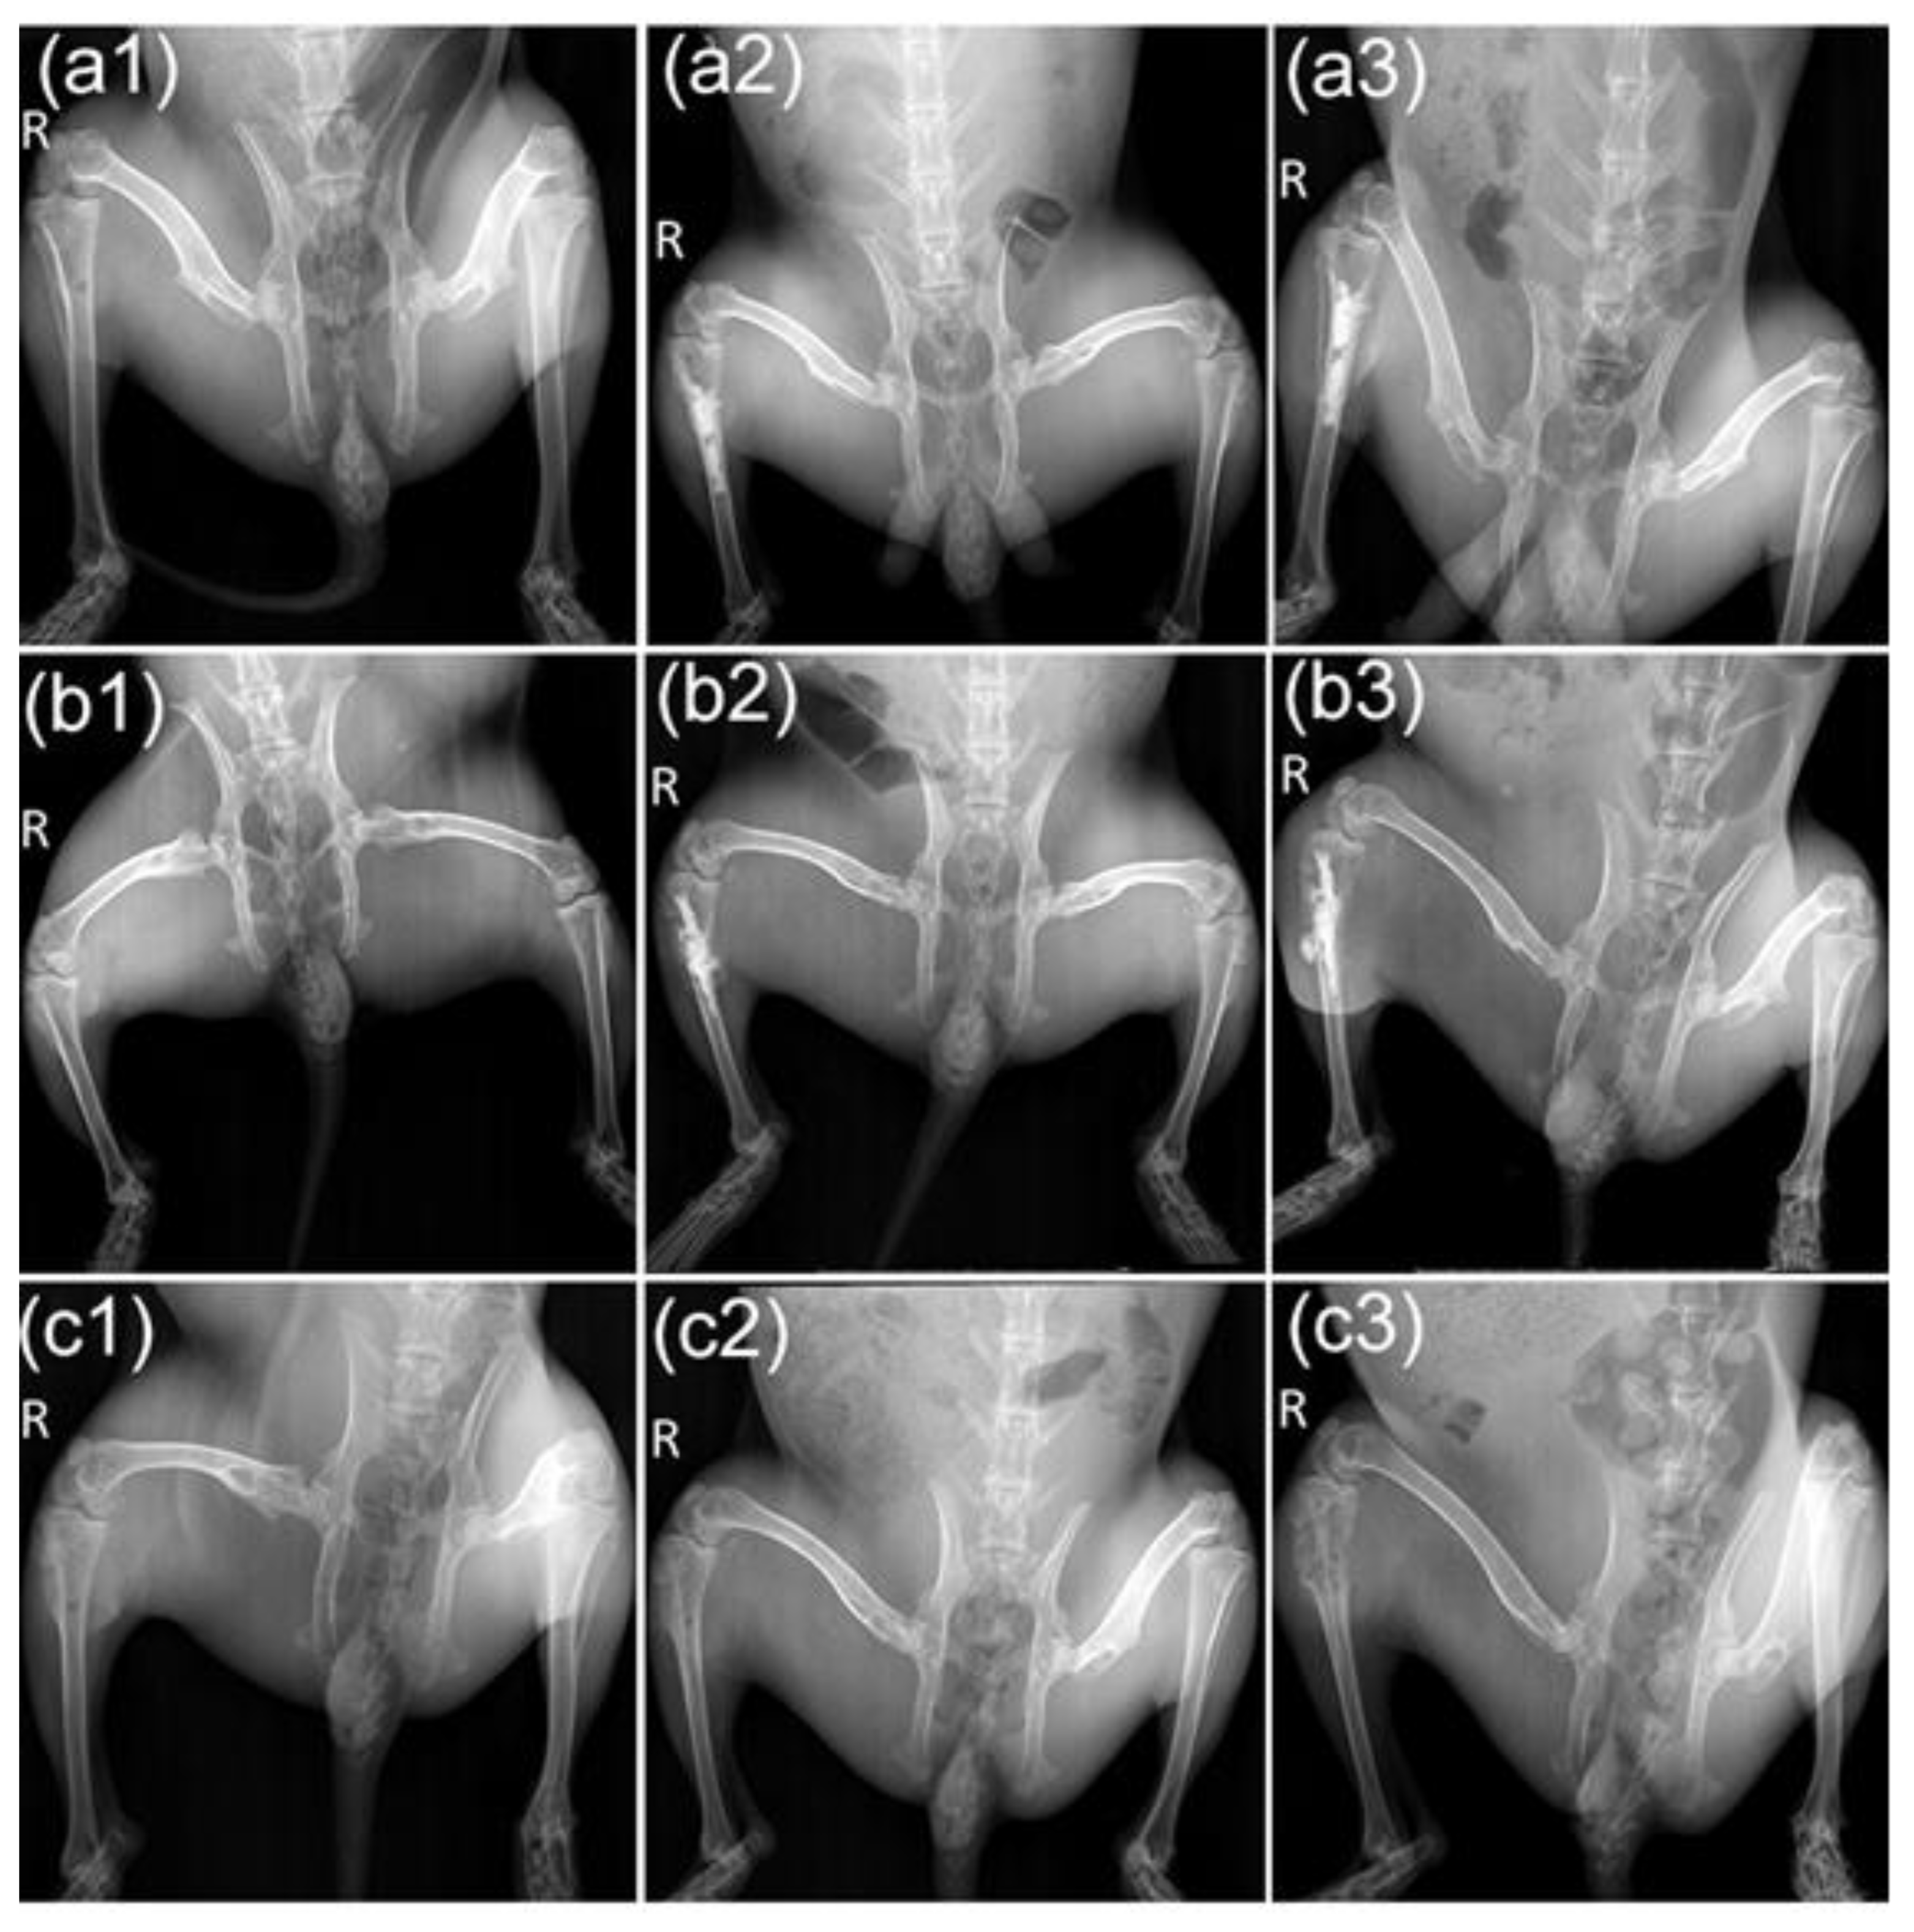

In addition, the incidence of pathologic fractures was 10% in the M-PMMA and control groups, which did not occur in the M-PMMA + AMF group. Furthermore, skeletal morphologies and bone resorption were evaluated by micro-CT after magnetic hyperthermia. Although the cortical bone thickness of tumor-bearing tibias in the M-PMMA + AMF group (Figure 6a1,b1,c1) was less than in the normal tibias (Figure 6a4,b4,c4), skeletal morphology still existed. However, the tumor-bearing proximal tibias in the M-PMMA (Figure 6a2,b2,c2) and control groups (Figure 6a3,b3,c3) were severely destroyed, the cortical bone was erosive, and the skeletal morphologies were almost destroyed. The bone volume of the tumor-bearing proximal tibias was measured by software (Figure 4d), and the results were tested with one-way ANOVA. The bone volume in the M-PMMA + AMF group was higher than in the other two groups (p < 0.05). Magnetic hyperthermia induced by PMMA-Zn0.3Fe2.7O4 bone cement can inhibit bone resorption.

Figure 6. Micro-CT image of the affected lower extremities in the different groups after magnetic hyperthermia. Sagittal section (a1), coronal section (b1), and cross section (c1) of the M-PMMA + AMF group. Sagittal section (a2), coronal section (b2), and cross-section (c2) of the M-PMMA group. Sagittal section (a3), coronal section (b3), and cross-section (c3) of the control group. Sagittal section (a4), coronal section (b4), and cross-section (c4) of normal tibias.